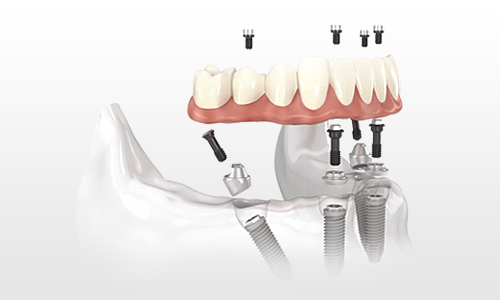

All-on-4全口种植牙恢复一口靓牙:

针对全口牙缺失的情况,比较推荐大家采用All-on-4 种植牙技术。圣洁口腔引进All-on-4技术利用四颗种植体即刻种出整排牙。由于所需种植体的减少,种牙无需植骨,使种植手术操作更简单、微损伤,所需时间更短,成功解决无牙颌种植难题。这项技术避免了痛苦、漫长、昂贵的牙骨移植,非常适合牙骨萎缩的无牙患者。

植牙流程:上午,上、下半口各植入4颗人工牙根;下午安装固定牙桥。术中及术后,几乎没有肿痛。